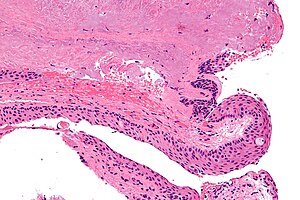

Pterygium. H&E stain. | |

| LM | hyaline material beneath epithelium, elastic fibres beneath the hyaline material, +/-inflammation, solar elastosis, dilated blood vessels |

Features:[4]

- Hyaline material beneath epithelium.

- Elastic fibres beneath the hyaline material.

- +/-Inflammation.

- Solar elastosis.[5]

- Dense gray/light brown acellular material.

- Dilated vessels.[5]